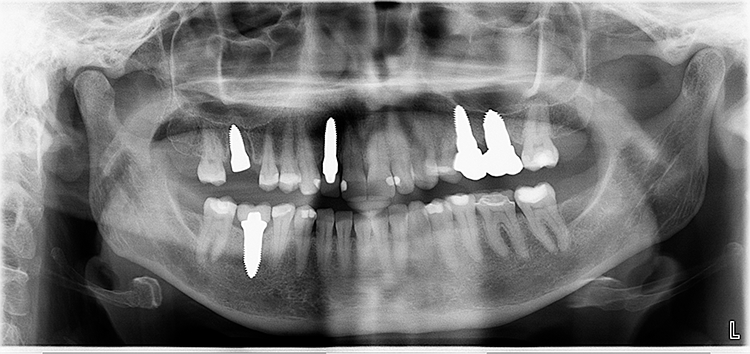

Abb. 2: Repräsentativer Fall von ABH Grad B Septus Typ II. a) Ansichten vor der Installation. Röntgenaufnahme der periapikalen Läsion an einem wurzelkanalbehandelten Molaren und klinische Ansicht der Typ-II-Socket nach der Extraktion. b) Die Ansichten nach der Installation zeigen das Implantat innerhalb des interradikulären Septums und das über dem Implantat platzierte A-PRF. c) Nachuntersuchungen nach 10 Tagen bzw. 2,1 Monaten. Die Röntgenaufnahme zeigt die Knochenbildung zwischen der Sinusmembran und dem apikalen Teil des Implantats. d) Jüngste Nachuntersuchung nach Einsetzen der Prothese.

Abb. 3: Repräsentativer Fall von Grad A Typ I. a) Präoperative Ansicht. Röntgenbild der periapikalen Läsion an einem wurzelkanalbehandelten Molaren. Die Höhe des Alveolarknochens zeigt Grad A an. b) Klinische und radiographische Ansicht der Implantatinsertion unter Verwendung einer Einheilscheibe mit großem Durchmesser (6×8 mm). A-PRF wurde um das Implantat und unter der Scheibe platziert. c) Nachuntersuchung nach 5,9 Monaten vor und nach der Zementierung und Aufbereitung. d) Jüngste Nachuntersuchung nach Einsetzen der Prothese

Abb. 4: Repräsentativer Fall von Grad A Typ III. a) Ansichten vor der Implantation. Röntgenbild der periapikalen Läsion an einem wurzelkanalbehandelten Molaren. b) Die Extraktionsalveole zeigt ein interradikuläres Septum vom Typ III (B).

Der Erfolg der Implantate wurde nach den Kriterien des Pisa-Konsensus von 2008 bewertet [9]. Alle Implantate wurden als Gruppe I mit einem durchschnittlichen marginalen Knochenverlust von –0,1775 + 0,68 mm nach 1 Jahr Implantation eingestuft, die einen Knochenverlust von < 2 mm und keine Empfindlichkeit, Beweglichkeit oder Exsudat aufwiesen.

Querschnittsbilder aus dem DVT zeigen eine hohe Genauigkeit und Zuverlässigkeit bei linearen Knochenmessungen im Zusammenhang mit der Implantatbehandlung [2]. Marginale Knochenniveaus wurden am Schnittpunkt zwischen der Längsachse des Implantats und der mesiodistalen Linie gemessen, die durch den größten krestalen Knochen auf jeder Seite des Implantats markiert ist und als Referenzpunkt für die Messung des Knochenverlusts bei Nachuntersuchungen dient. Trotz der begrenzten Anzahl von Implantaten und der Beschränkungen der Studie wurde eine Überlebensrate von 100% erreicht.